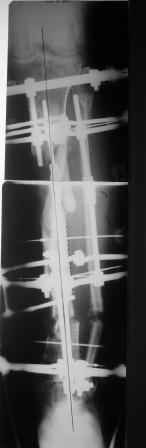

Коллеги!Позвольте продолжить обсуждение темы «ложный сустав левой голени.» Больной К 45 лет, начало см. http://www.weborto.net/forum/1228422607/ И рассказать о результатах проделанной работы. Остановились на следующей тактике 1) Наложить Аппарат Илизарова. В аппарате восстановить оси трех смещенных относительно друг-друга фрагментов большеберцовой кости. Устранить вальгусную деформацию дистального отдела большеберцовой кости. Что и было выполнено. - Была выполнена репозиция в аппарате (рис1) 2) После репозиции более очевидна стала проблема дефекта кости в верхней трети голени, два фрагмента свободно лежат. Остановились на варианте перехода на интрамедуллярный синтез стержнем с покрытием костный цемент+ванкомимцин и замещении дефекта с помощью транспорта фрагмента (рис 2) 3) Третьим этапом наложили модуль на промежуточный фрагмент.(рис 3) И начали его транспорт на стержне в проксимальном направлении. (рис 3 а) Надеемся что «вырастет» регенерат в дистальном отделе, а в проксимальном отделе фрагмент «упрется» и прирастет. Хочу сказать слова благодарности за обсуждение на форуме этого случая. Особые слова благодарности Иванову Павлу Анатольевичу!!! Он помогал Словом, а самое главное делом. Приезжал, оперировал! За что ему нижайший поклон! С ув Коробушкин Г